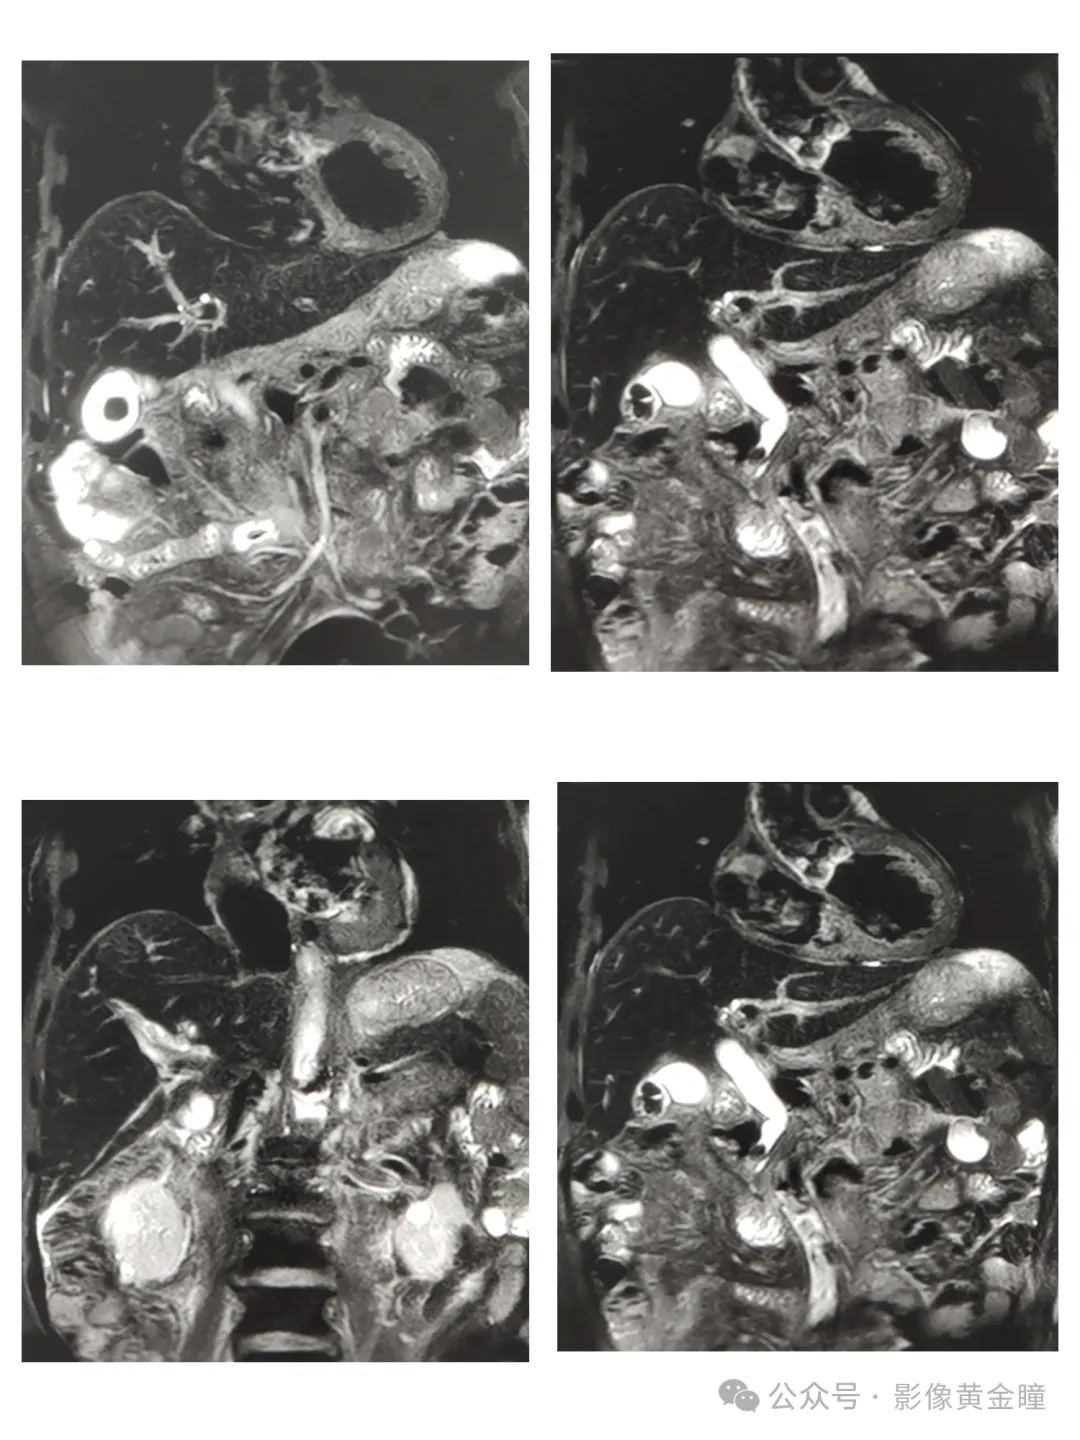

Glisson鞘水肿CT平扫表现为沿肝Glisson鞘分布的低密度区,MRI表现为T2加权像显示门静脉周围高信号带。

Case2、女 87,反复右上腹疼痛一年,加重5天。

Case3、男,72 腹痛5小时

Case4、女,83 上腹部疼痛不适20天,加重7小时。